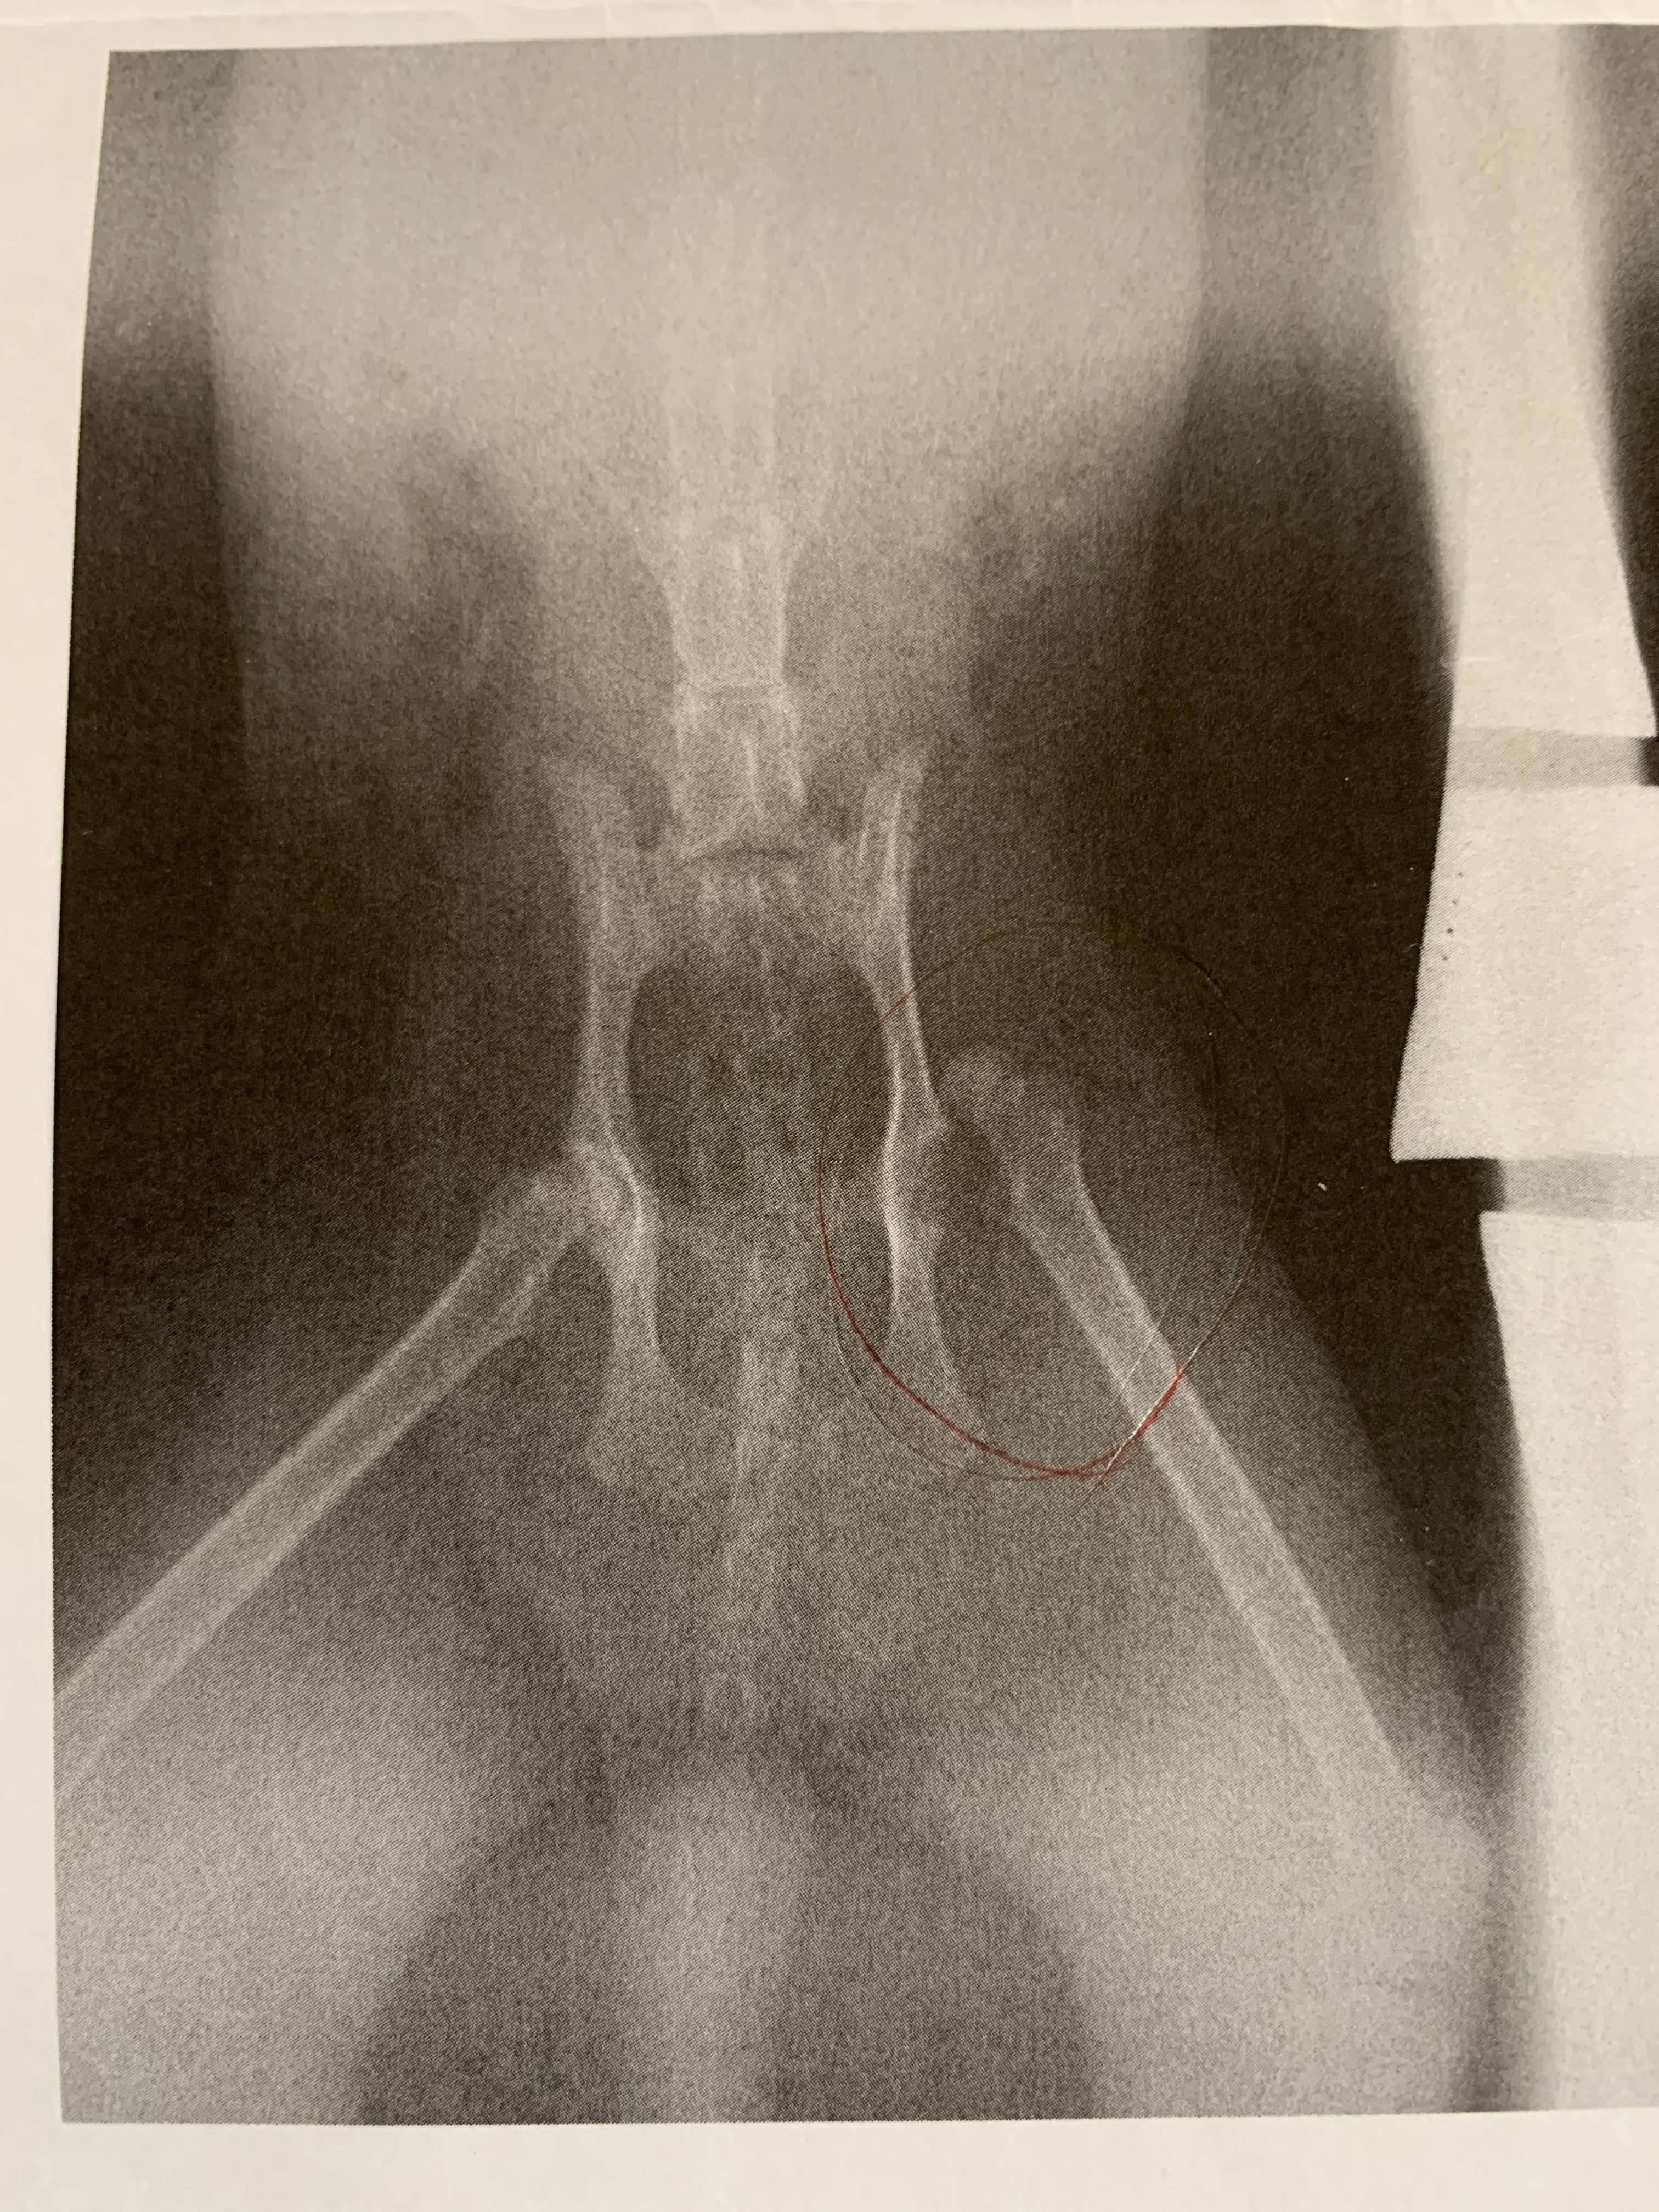

おそらく交通事故にあったようで、下半身不随で排泄は垂れ流し、左股関節脱臼もあり愛護センターで整復してもらいましたが再脱臼、引き受け当初は両後ろ足の浮腫みもひどく、後に右大腿部の皮膚と筋肉は壊死、しばらくしてから尻尾も半分壊死という状態でした。また、野良猫だったようで気性も荒くシャーやパンチはもちろん、噛みつきも少しありました。

左股関節の脱臼は根本的治療をするため、大腿骨頭切除手術をすることになりました。股関節にはめる部分の骨を切り取る手術です。こうすることで大腿部と股関節の骨はくっつかなくなりますが、それを補うように周りの組織がカバーして歩けるようになるとの事でした。結果、ひかりも歩いております。

股関節脱臼